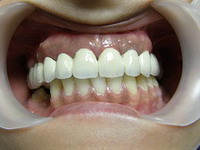

Situatie initiala

Coroane ceramica pe suport zirconiu